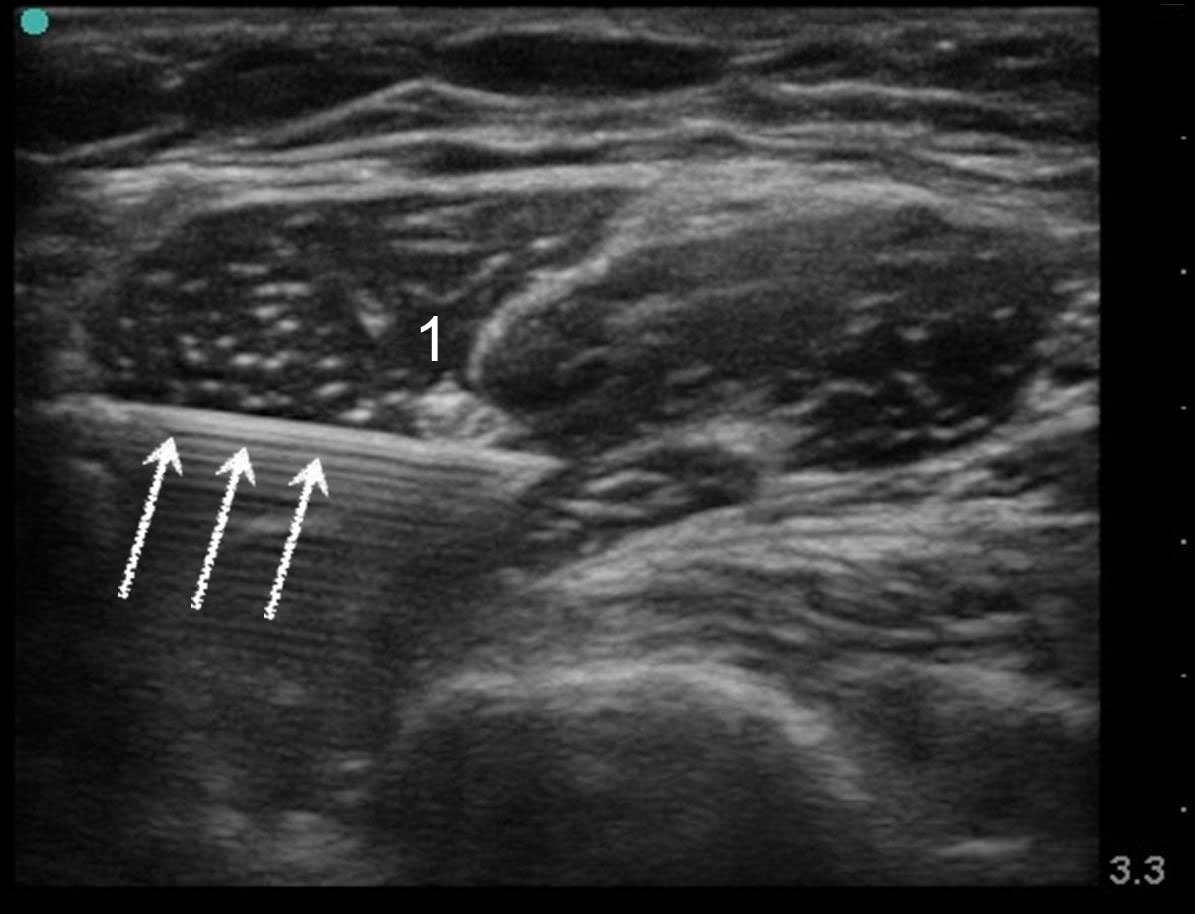

肌皮神经 2 图像

肌皮神经

白色箭头:针